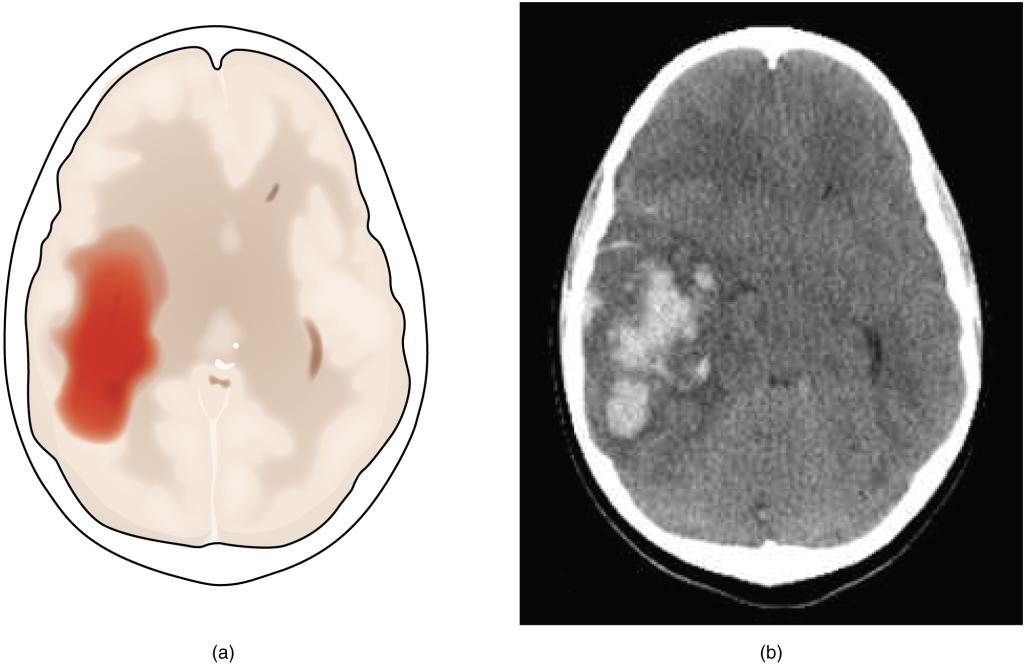

A hemorrhagic stroke is bleeding into the brain because of a damaged blood vessel. Accumulated blood fills a region of the cranial vault and presses against the tissue in the brain (Figure 14.2.3). Physical pressure on the brain can cause the loss of function, as well as the squeezing of local arteries resulting in compromised blood flow beyond the site of the hemorrhage. As blood pools in the nervous tissue and the vasculature is damaged, the blood-brain barrier can break down and allow additional fluid to accumulate in the region, which is known as edema.

The left panel of this image shows an image of the brain with a region in red. Arrows pointing towards this region indicate a hemorrhage associated with a stroke. The right panel shows a hemorrhage as it might appear on a CT scan.

Figure 14.2.3 – Hemorrhagic Stroke: (a) A hemorrhage into the tissue of the cerebrum results in a large accumulation of blood with an additional edema in the adjacent tissue. The hemorrhagic area causes the entire brain to be disfigured as suggested here by the lateral ventricles being squeezed into the opposite hemisphere. (b) A CT scan shows an intraparenchymal hemorrhage within the parietal lobe. (credit b: James Heilman)